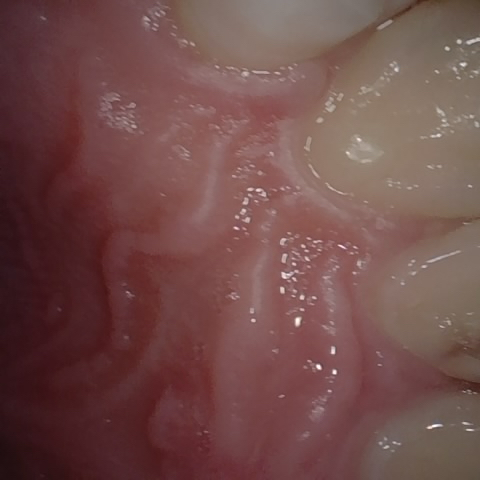

Annotated as "Good"